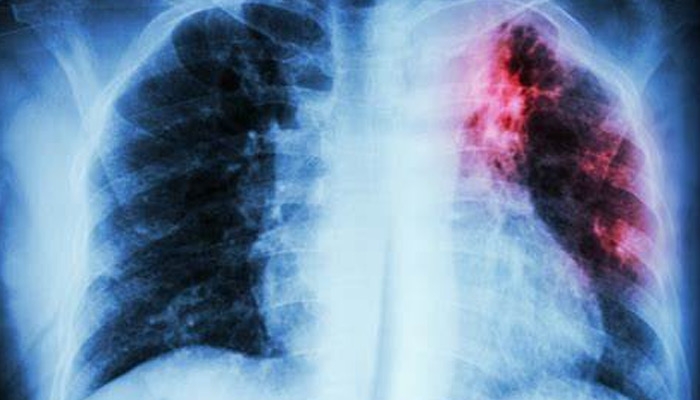

“TB kwenye Mkoa wa Simiyu inaongezeka (maambukizi) kutokana na shughuli mbalimbali za kiuchumi, hususani wachimbaji wadogo wadogo wa madini na kambi za uvuvi kule Busega. Mwaka jana tulikuwa na wagonjwa 3,600 ikilinganishwa na mwaka juzi ambapo tulikuwa na wagonjwa 2,700,” amesema Emmanuel.

Mratibu huyo ameogeza kwamba kwa mujibu ripoti ya Shirika la Afya Ulimwenguni (WHO) kwa mwaka 2021, Tanzania ilikuwa na watu 132,000 walioambukizwa ugonjwa huo, na kwamba mpango wa Taifa ni kutokomeza ugonjwa wa Kifua Kikuu ifikapo mwaka 2030.